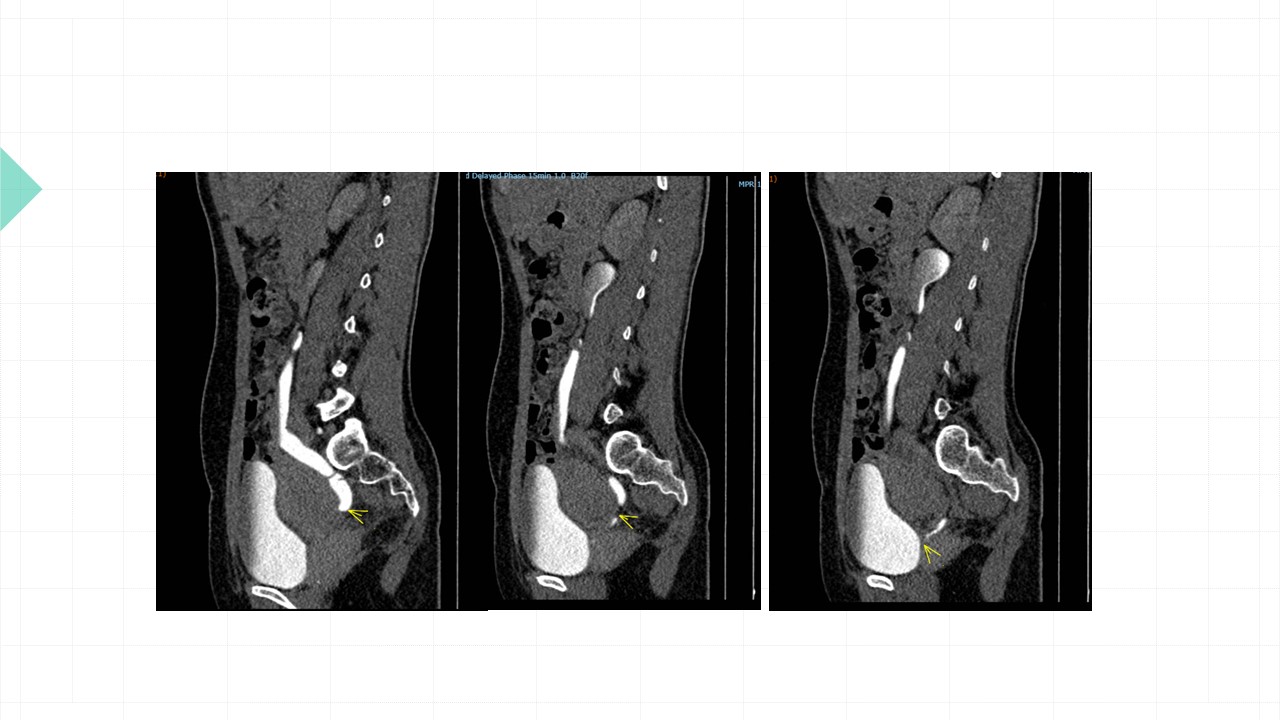

Vai trò cộng hưởng từ trong đánh giá lạc nội mạc tử cung

Từ khóa: Vai trò cộng hưởng từ trong đánh giá lạc nội mạc tử cung